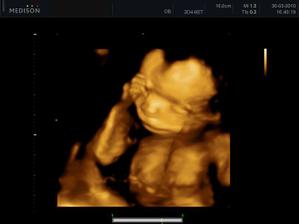

30.03. - (20+5), tak na dnešní kontrole dopadlo všechno na 1*, vážíme už 380g a z našeho Marečka se nakonec vyklubala Amálka, která měla mezi nožičkama zamotenej pupečník 😀 Pan doktor říkal, že tentokrát, je to opravdu na 100%

27.04. - (24+5) video, tak z videa nakonec sešlo. Dohodli jsme se s panem doktorem, že se mu ozvu, tak za 14 dní, až Karolínka ještě povyroste. Teď má v bříšku ještě moc místa a nebylo by to úplně ono. Tak jsme alespoň dostali několik foteček a dva doktoři nám potvrdili, že jde skutečně o holčičku.